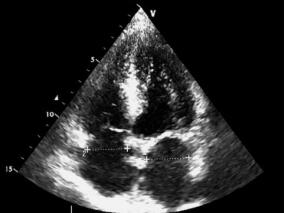

完全符合诊断标准的主动脉粥样硬化复杂斑块致脑栓塞…

1小时条评论1 病例简介 患者男,74岁。因头晕、视物不清1日于2009年5月28日入院。患者于入院前一天在行走中突然感到头晕、视物不清,无头痛、恶心、呕吐及其他不适,次日到当地医院就诊,检查发现左眼视野中心暗点,颅脑MRI:双侧大脑后动脉和大脑中动脉供血区散在新鲜梗死灶...